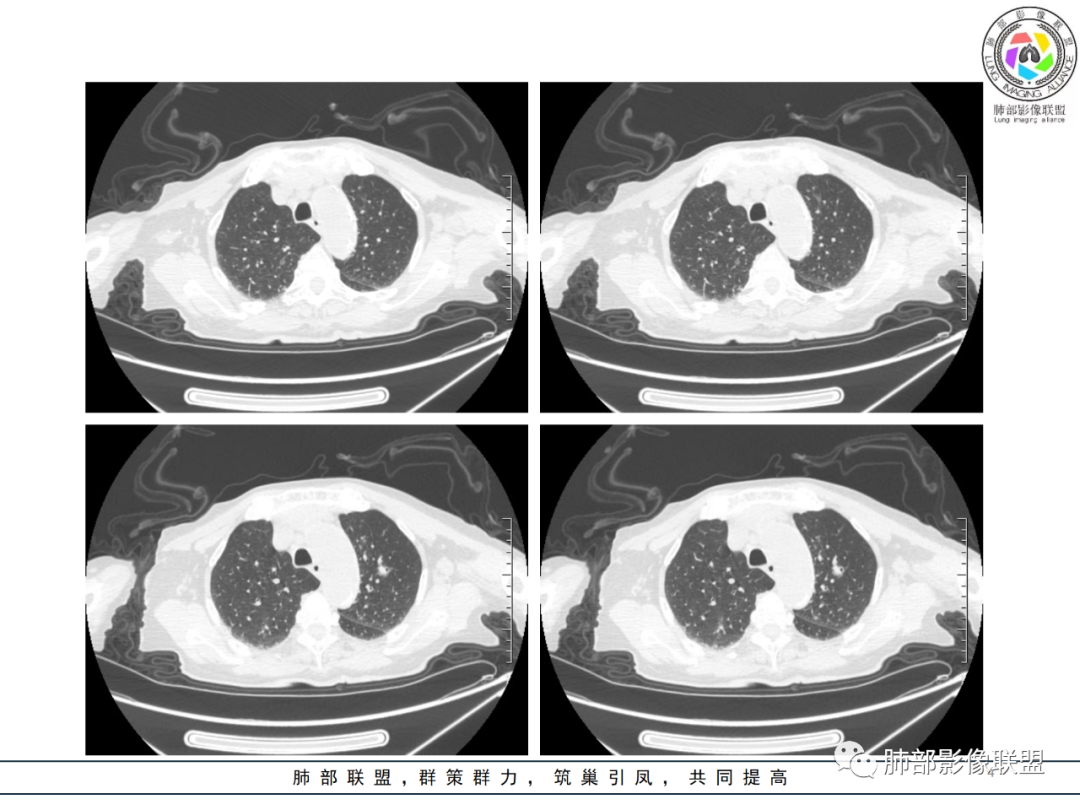

影像资料

老年女性,发热起病,两肺散在斑片状影,三个月后两肺病灶进展,支气管血管束增厚,结合发热病史、实验室检查LCH增高,肾脏及腹膜后淋巴结肿大,结合以上综合考虑符合淋巴瘤表现。

老年女性 3个月前发热,双肺支气管血管束增粗改变。3个月后再次发热,影像见双肺广泛支气管血管束明显增粗,较前进展,并延续进入纵隔,另外增强见双肾周增多软组织密度,左肾明显且肾门处形成肿块样改变。综合考虑肿瘤性病变可能性大,1.小圆细胞肿瘤类病变,淋巴瘤?2 全身组织细胞类病变,如ECD,需要看看骨组织有无问题。3 左肾恶性肿瘤并淋巴道播散,如弥漫性尿路上皮癌。最后考虑 淋巴瘤>ECD>左肾恶性肿瘤并转移。

老年女性,发热,白细胞不高,CRP增高,LDH增高,糖尿病。两肺支气管血管束周围实变、GGO,支气管相对通畅,提示淋巴间质或血管来源。三个月明显进展伴双肾浸润性病变、腹膜后淋巴结肿大,轻-中等程度强化。考虑淋巴瘤,鉴别系统性疾病(IgD4、血管炎)。

老年女性,双肺支气管管壁增厚,沿血管束走形分布结节及斑片影,复查病灶增多增大,部分呈点晕征改变,腹部左肾盂软组织密度影,周边淋巴结增大。考虑肿瘤并肺内转移,淋巴瘤?鉴别真菌感染,曲霉菌?

女性,82岁,发热5天入院,双肺自肺门处血管束增粗,扭曲,三个月后多发结节及实变影,延支气管血管束分布,部分支气管近端堵塞,左肾异常占位?伴有双侧肾上腺增粗,实验室血象略高,考虑IgG4?结节病?淋巴瘤?进一步穿刺活检。

82岁女性,反复发热入院,查外周血白细胞升高,抗生素治疗可缓解,支持细菌感染性发热,结合肾脏肿瘤,考虑泌尿系感染发热;CT提示双肺多发毛玻璃影,右下肺多发大结节影,3月复查,双上肺毛玻璃影/混合毛玻璃影增多,部分呈点晕征,右下肺多发肿块,可见支气管穿行,双下肺中轴间质增厚,左肾占位,肺部病变考虑:1.淋巴瘤 2.肾癌肺转移

老年女性,近期反复的发热,胸部CT基础尚可,心影增大,双肺下叶血管束增粗,3个月后复查 提示双肺多发磨玻璃密度影,并有磨玻璃影内部血管的穿行,双肺下叶血管束的增粗,纵隔窗下未见纵隔肿大的淋巴结,血管通畅,未见血管壁的增厚,左肾肿瘤?肺内病变不符合支气管束分布,暂不考虑吸入性,考虑淋巴管或血管源性病变。总体考虑非感染性病变可能性大,血管炎?淋巴瘤?

老年女性患者,发热就医,两肺片状影,沿支气管血管束分布,炎性指标升高,糖尿病基础,首诊考虑肺部感染合乎情理,这也是常见病!事实上,患者抗感染治疗好转出院。

三月后患者再次因发热就医,病灶在“原址”基础之上范围扩大,病灶增多(而非此起彼伏),就有些不同寻常,仅如此高龄,如此大范围感染,持续三月之久?太难以想象。